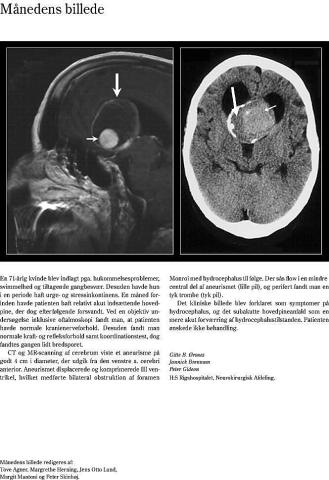

Ugeskr Læger 2003;165(5):